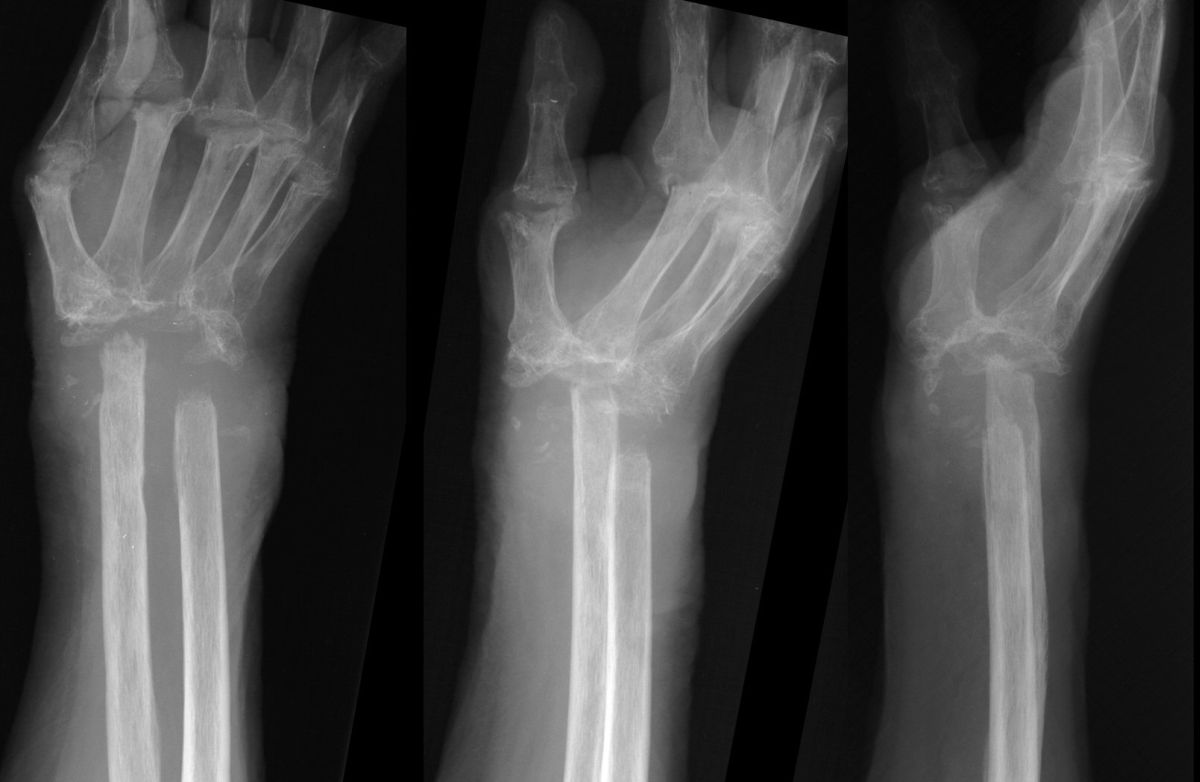

Late result, showing graft incorporation and remodelling.

Highslide